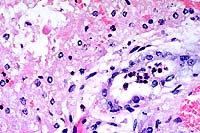

40x

obj.

- Case 21-1. Liver. Bile ducts contain neutrophils and

are surrounded by edema. There is degeneration and necrosis of

adjacent hepatocytes.

3. Liver: Necrosis, disseminated.

4. Liver: Cholangiohepatitis, neutrophilic, diffuse, mild.

- Conference Note: Participants identified extensive,

sometimes submassive, hepatic necrosis and neutrophilic portal

inflammation that multifocally filled bile ducts and disrupted

the limiting plate. Viable hepatocytes were present among individually

dissociated and necrotic hepatocytes. In addition to necrosis

of the tubular epithelium in the kidney, tubular regeneration

and casts were observed.